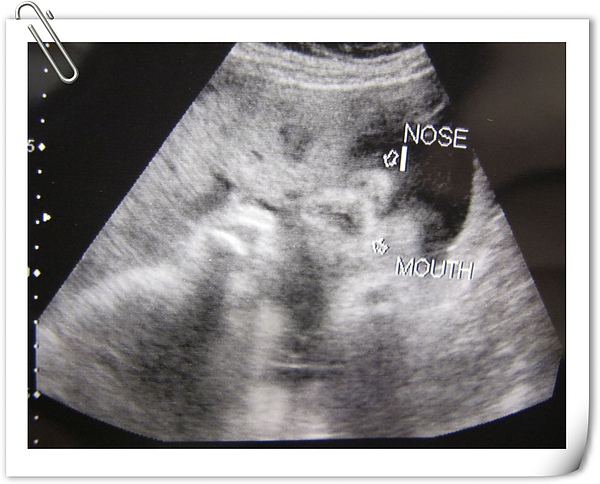

小臉,超音波師說他眼睛有張開一點點

我問超音波師說鼻子算大嗎??

超音波師回答我:還好

這......我該如何跟米拔交待呀~~~~

這張是小嘴有張開喝羊水的樣子~~